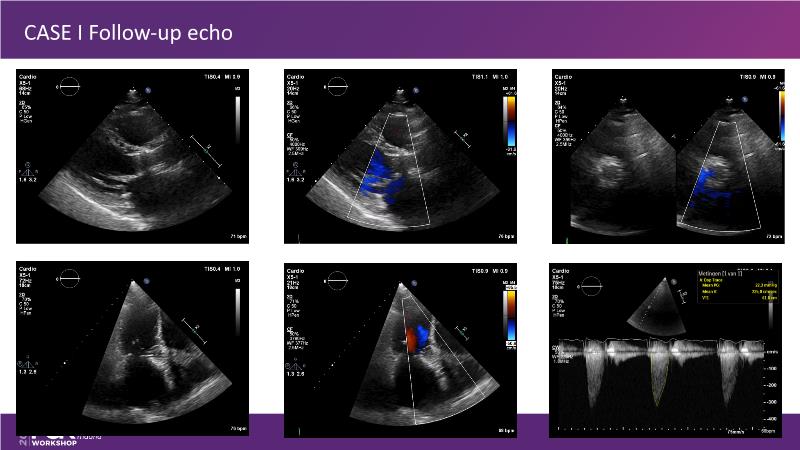

Explore cutting-edge transcatheter valve interventions for mitral and aortic valve disorders, including valve-in-valve procedures and management strategies for paravalvular leakages, and learn about diagnosing and treating mitral annular calcification and transcatheter options in infective endocarditis.

- To get tips and tricks for guidance of transcatheter intervention